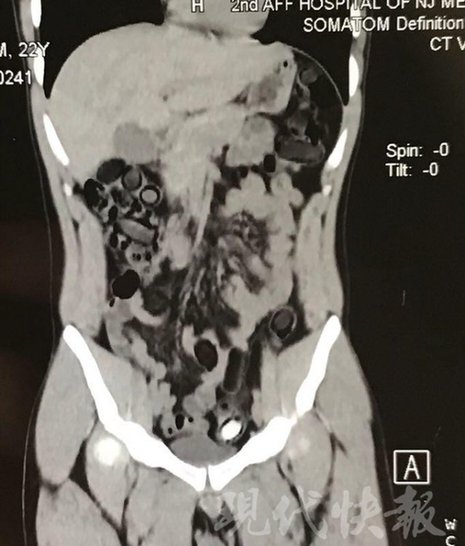

小伙體內(nèi)藏毒300余克 CT掃描圖密密麻麻

由于毒品在體內(nèi)一旦泄露有可能致命,警方第一時間將阿永帶到醫(yī)院進行檢查。CT 掃描的結(jié)果顯示,阿永體內(nèi)布滿了密密麻麻的白色圓柱狀固體,就像一粒粒的蠶蛹。在南京市公安局鼓樓分局二板橋派出所,阿永分四次排出了毒品,毛重369.99克。經(jīng)訊問,阿永交代了自己全部的犯罪事實。目前,阿永已被刑事拘留。